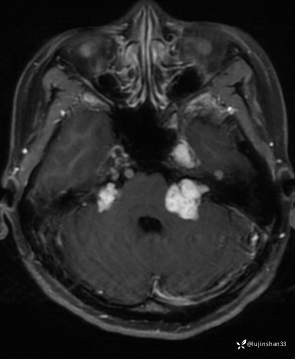

第二次术前CT及MRI